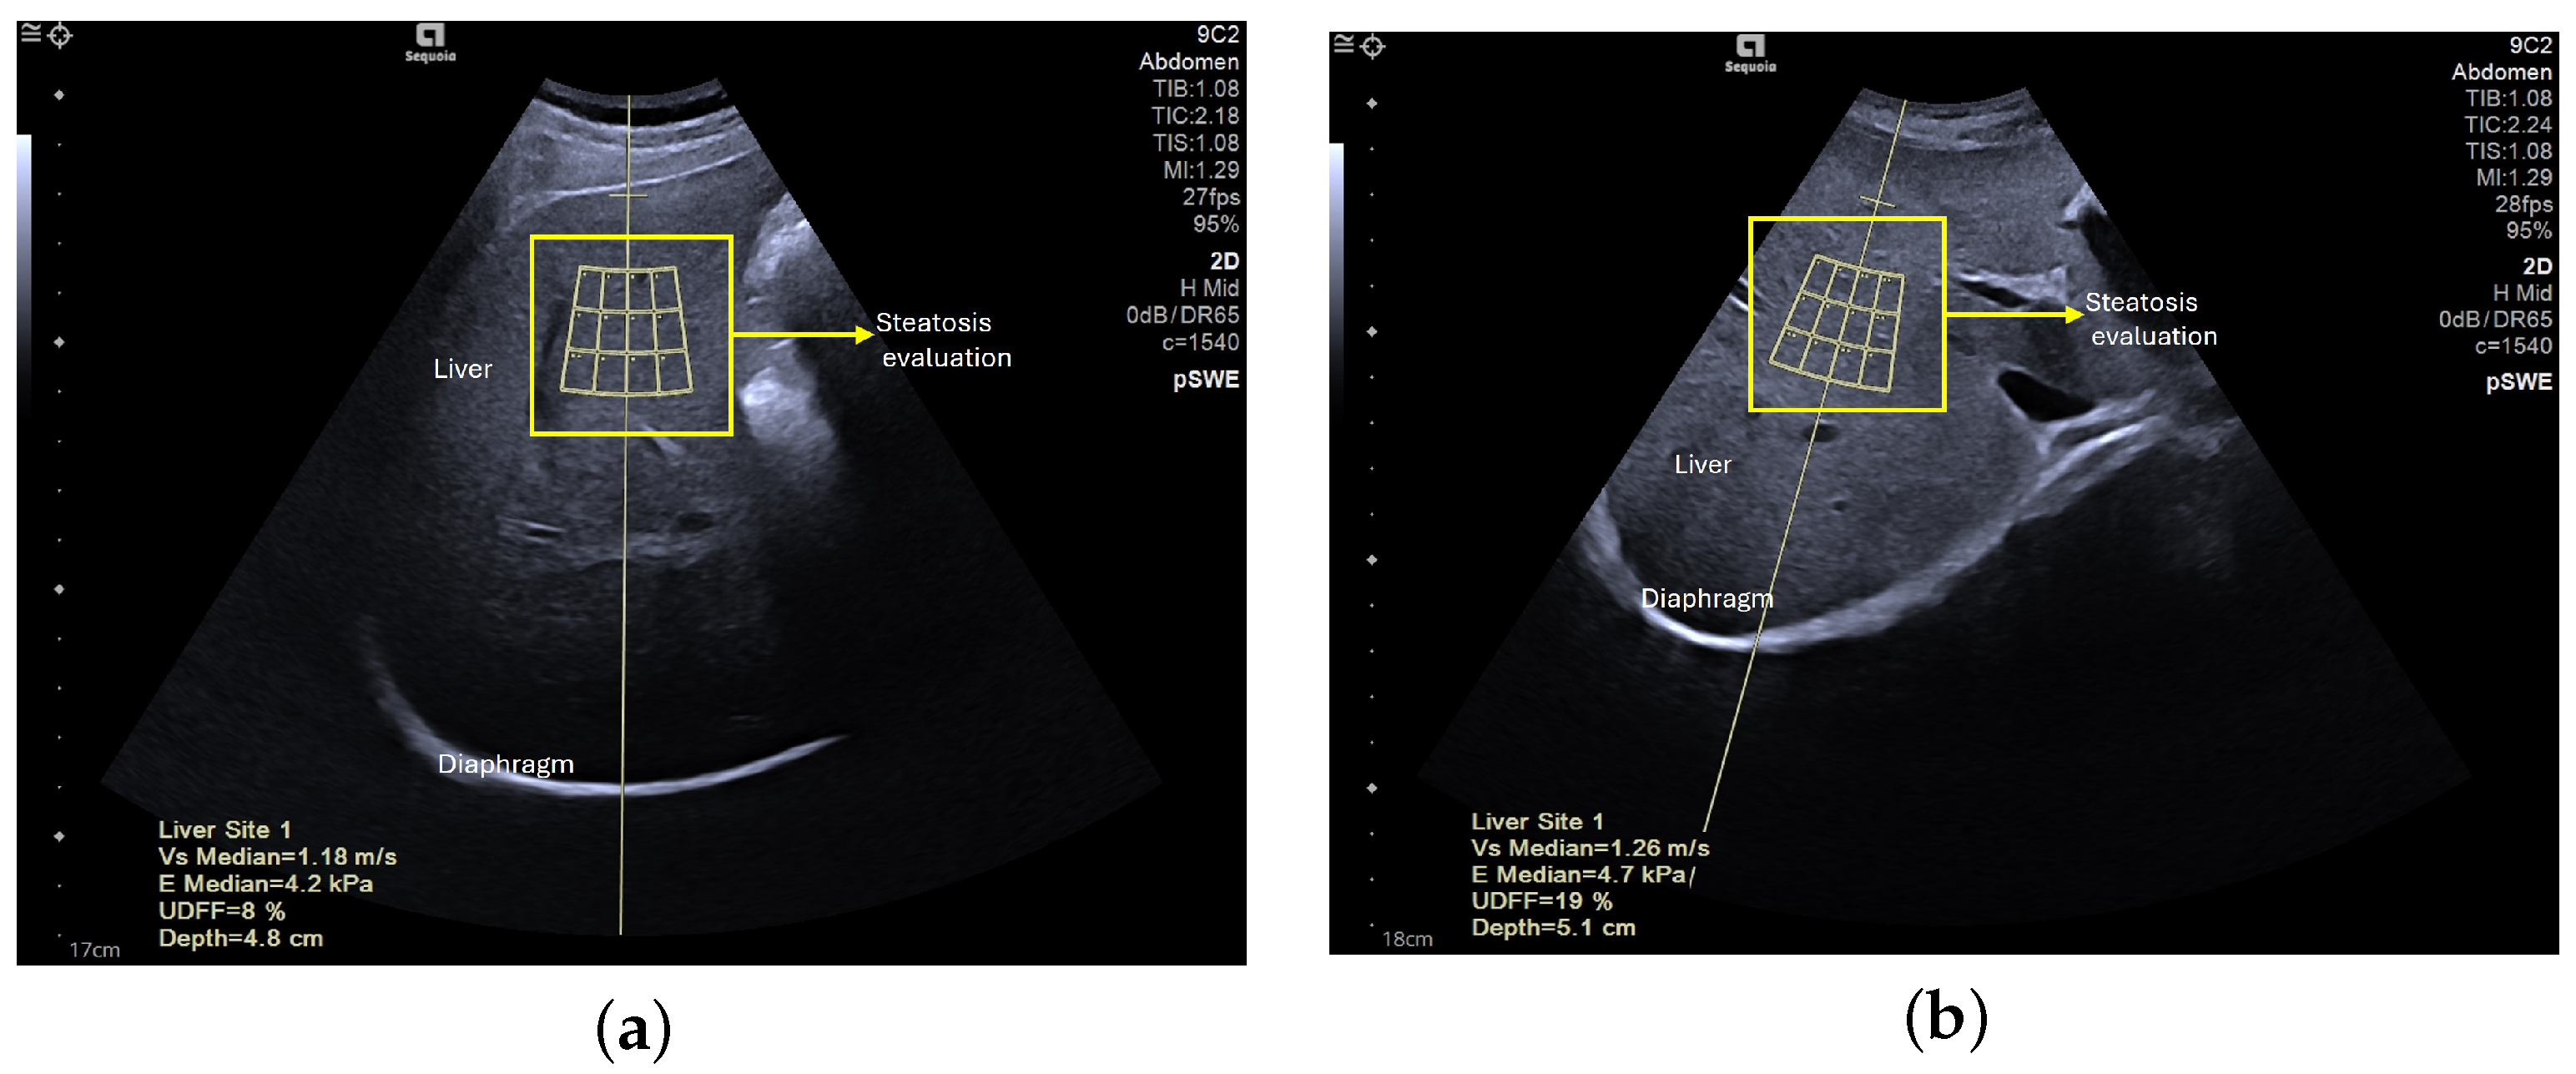

The second set of images acquired for this study is composed of 96 elastography images—61 of NAFLD patients and the remaining 35 of healthy subjects. These were obtained at the School of Health Technology from Coimbra, extracting data from 50 participants, ranging from 18 to 50 years old. A consistent procedure was used to acquire the images for the dataset. Each subject was studied by a single operator who performed fist the US assessment of the liver steatosis in B-mode. A portable ultrasound (Acuson P500) with a convex transducer (5.2 MHz), was operated by one experienced researcher (>20 years). The collection was conducted during rest. Shear-wave elastography (SWE) data collection was conducted using the abdomen shear module of an Acuson Sequoia Ultrasound System 2018; this device was coupled with a convex transducer (9C2 Mhz). Figure 2 and Figure 3 are examples of acquired images. In order to maintain consistency across all acquisitions, a quality factor of over 65 was consistently achieved, enhancing the accuracy of classification and analysis, as well as image quality. The settings were maintained at a frame rate of 27 fps (frames per second) and a vertical scale (V scale) of 95%.

Figure 2. Mode B intercostal scan of the right lobe of the liver, acquired with the Acuson Sequoia ultrasound system, showing the liver: (a) without steatosis, (b) with steatosis.